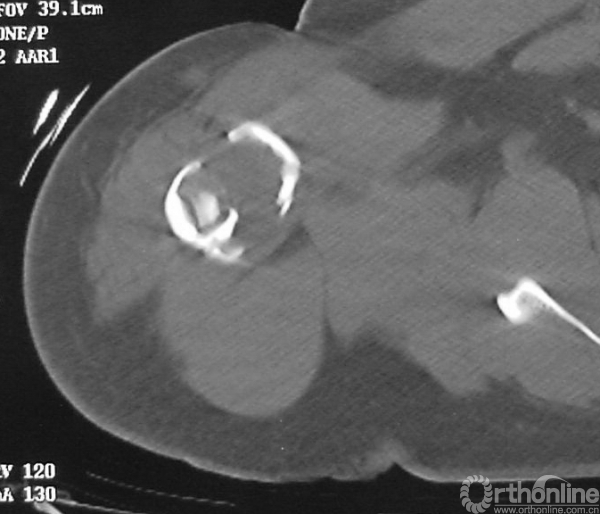

图13-4 病例二伤后CT轴位骨窗

病例二:X线平片见病变有膨胀性表现,病变内基质均匀,可见皮质骨折片,边界较清楚,除骨折导致的皮质骨连续性中断,未见皮质骨溶骨性破坏。提示疾病没有侵袭性表现。